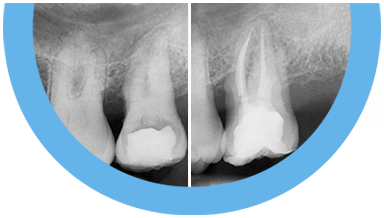

Paciente de 76 anos do sexo masculino

Motivo da consulta: Paciente desdentado total, procurava colocar dentes.

Plano de tratamento: Colocação de 4 implantes superiores e 2 implantes inferiores. Confeção de uma barra superior e colocação de 2 locators® na parte inferior. Confeção de uma prótese superior e outra inferior removível, com encaixes na barra e locators®.

A escolha deste plano de tratamento deve-se ao facto de o paciente querer uma solução total, mas não completamente fixa, uma vez que não tinha muita destreza manual para higienizar uma prótese fixa. Desta forma, conseguiu uma solução bastante retentiva (devido aos encaixes) mas que consegue remover para uma higienização correta.